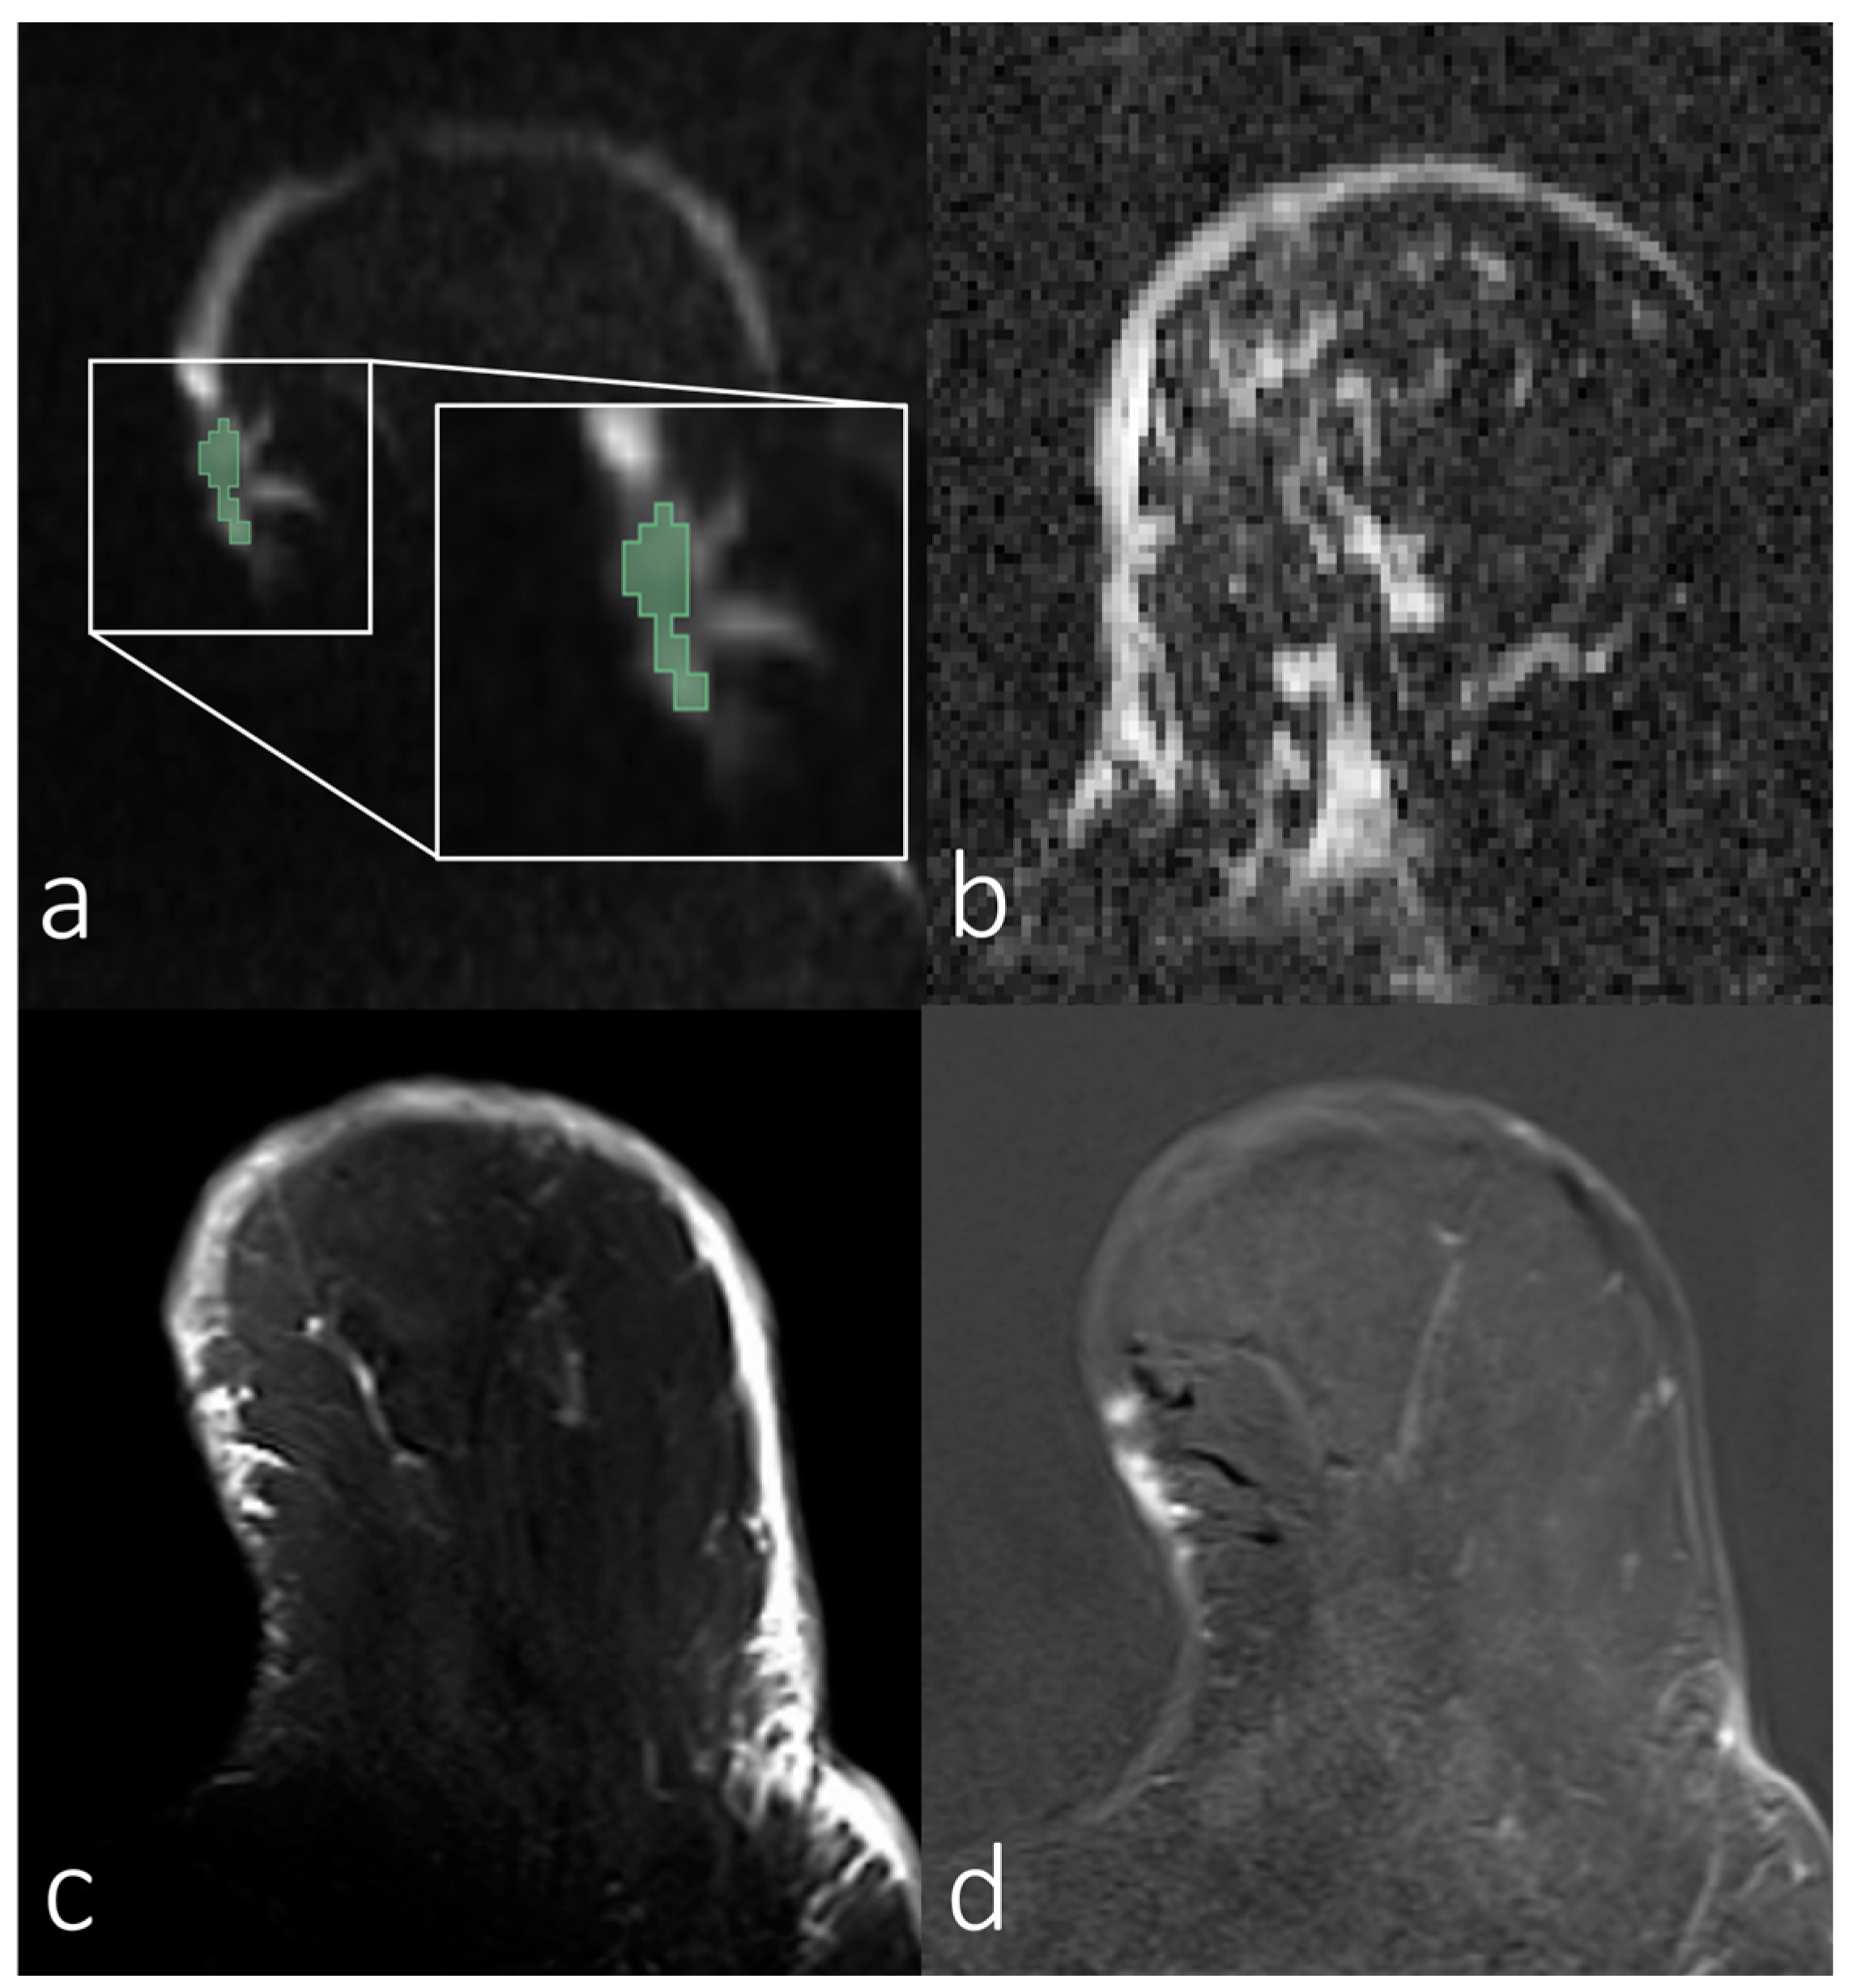

1. Introduction

2.2. MRI Protocol

2.3. Data Processing

2.4. ADC Calculation

2.5. SNR Estimation